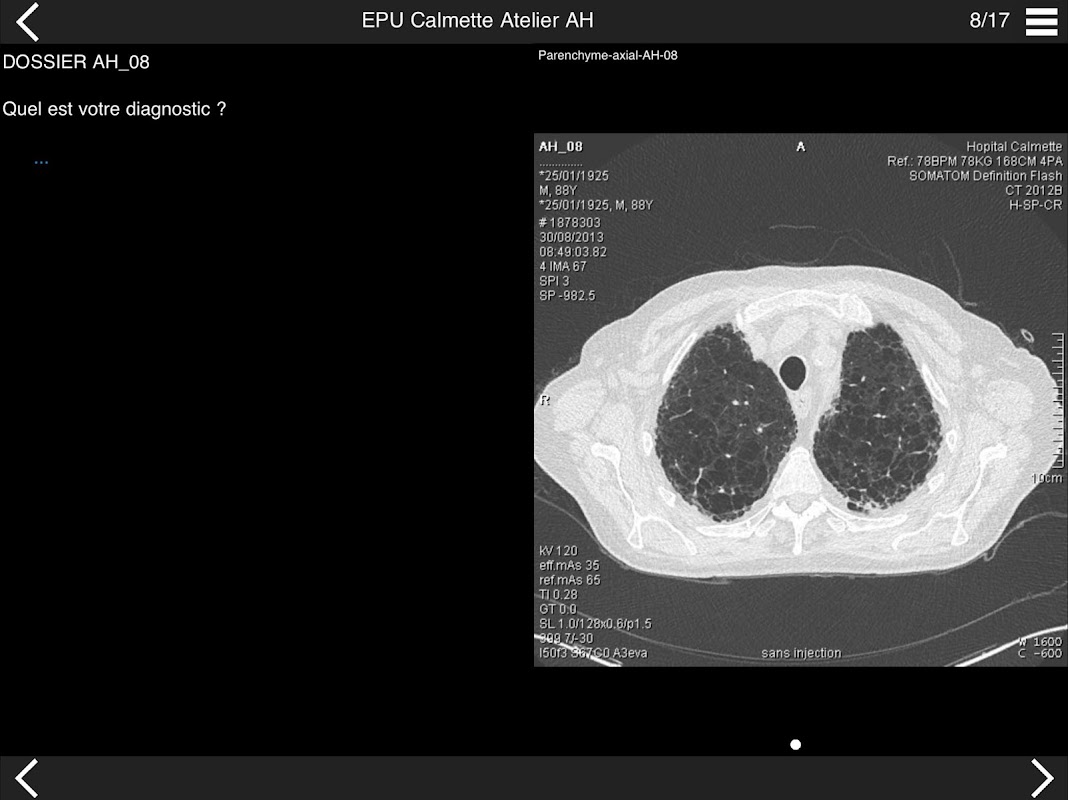

* Pathologie interstitielle : lésions élémentaires et « patterns »